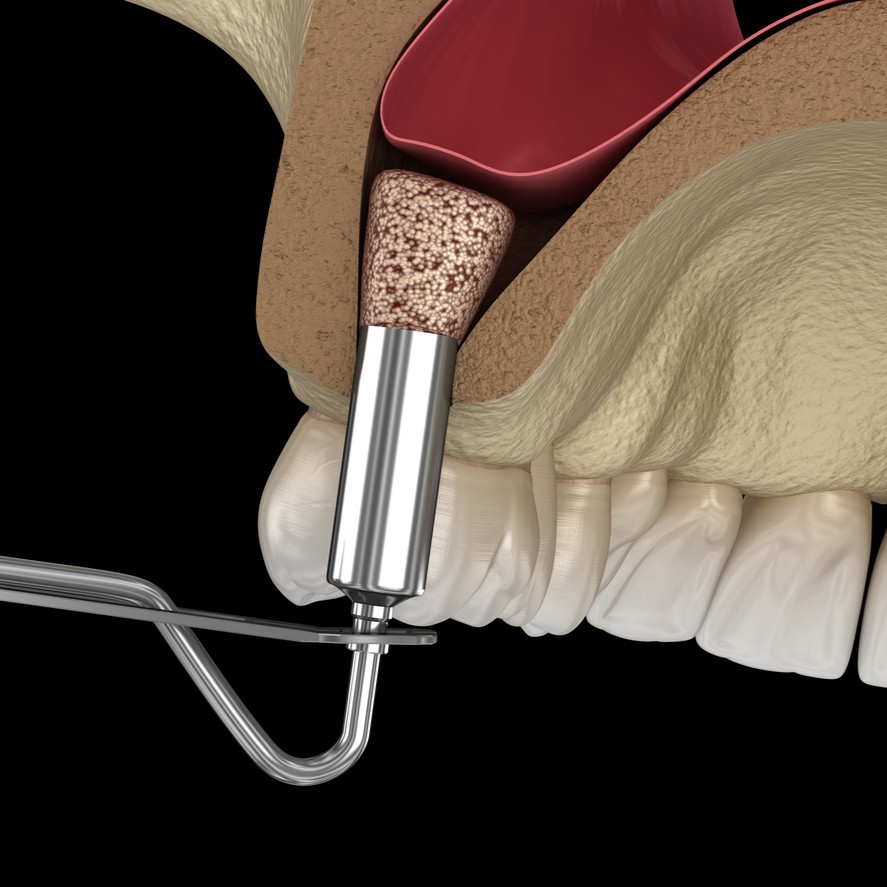

Chirurgie pré-implantaire

Préparer l’os à recevoir un implant

Lorsqu’une perte osseuse empêche la pose directe d’un implant, la chirurgie pré-implantaire permet de recréer les volumes nécessaires. Elle regroupe différentes techniques comme la greffe osseuse ou l’élévation du plancher sinusien (sinus lift), qui visent à redonner à l’os une densité et une hauteur suffisantes. Ces interventions, réalisées avec des biomatériaux de dernière génération, garantissent la stabilité et la longévité des implants posés par la suite. Elles constituent une étape clé pour assurer un résultat durable et esthétique.